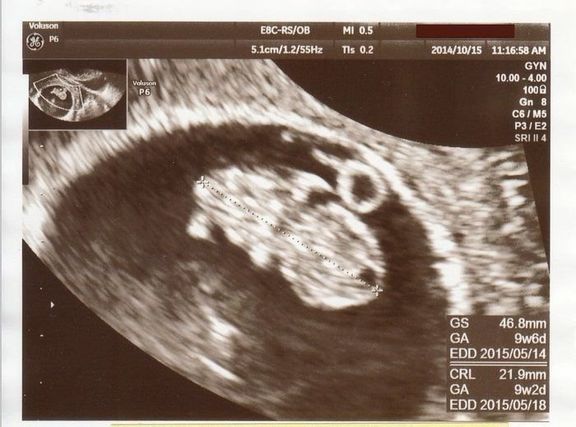

命の始まりは神秘的!2D・3D・4Dのエコー写真で見る「私と赤ちゃんの実録260日」 -

"おなかの中はどうなっていくの? エコー写真で振り返る、高齢ママのはじめての妊娠生活" -